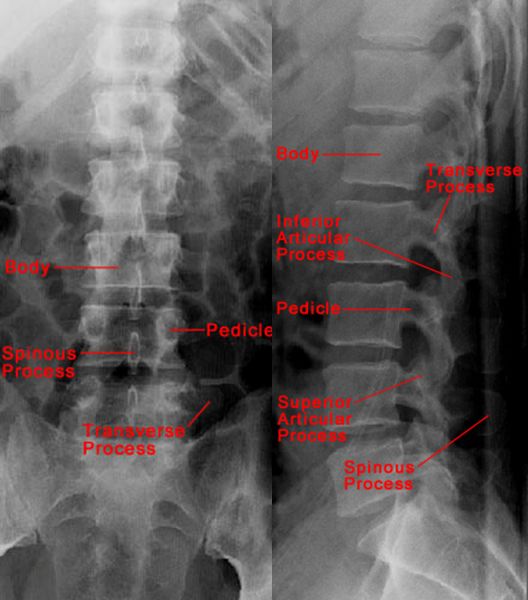

正常腰椎

L5腰椎骨折